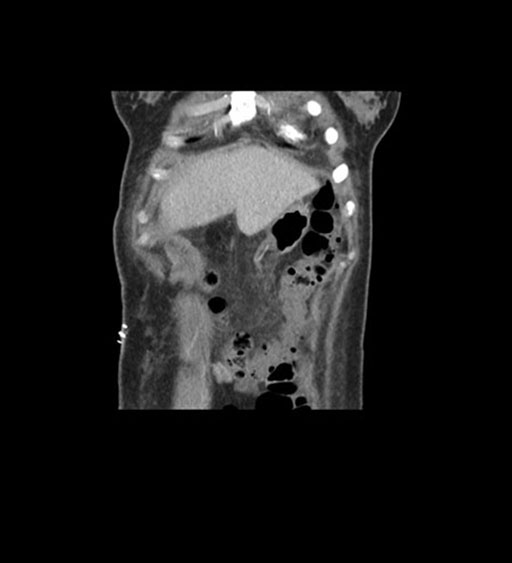

Coronal Arterial